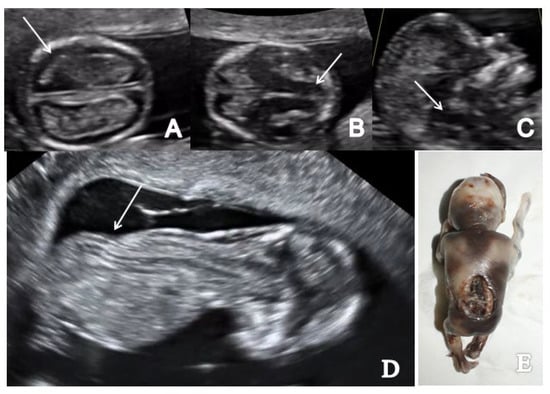

3.5. Holoprosencephaly

Cerebral parenchyma, ventricular system and midline structures were strongly affected in all three cases of holoprosencephaly detected in the FT. A fusion of the anterior horns of the lateral ventricles and the absence of the butterfly sign of the fetal brain was described in all cases diagnosing alobar holoprosencephaly. One case of alobar holoprosencephaly is also associated with proboscis and extreme hypotelorism–synophthalmia (Figure 7).

Figure 7.

A case of alobar holoprosencephaly diagnosed at 12 weeks + 5 days (Case 9): (A) transverse view of the abnormal brain cavities; (B) sagittal view of the fetal head showing proboscis (arrow); (C) frontal view of the fetal face showing extreme hypotelorism (arrow); (D) frontal view of proboscis (arrow); (E,F) specimen presentation aspect after medical TOP confirming proboscis and hypertelorism.